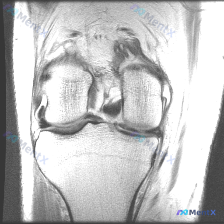

膝关节冠状位MRI发现内侧半月板高信号,帮看看是不是撕裂?

最近拿到一份膝关节单幅冠状位T2加权MRI,问题是找半月板潜在异常,整理了分析思路和大家分享一下。

这份是膝关节冠状位T2加权MRI扫描,我先把所有结构的评估整理出来:

- 骨骼结构:股骨远端、胫骨近端骨皮质清晰,骨髓信号正常,没有水肿、破坏或者占位

- 周围软组织:肌肉、皮下组织没有水肿或者占位

- 交叉韧带:冠状位显示不全,但可见部分连续性尚可

- 副韧带:内外侧副韧带走行正常,信号均匀,没有水肿断裂

- 关节软骨:股骨髁软骨轮廓平整,没有明显剥脱缺损

- 关节腔:没有明显异常积液

- 半月板:外侧半月板形态信号都正常;内侧半月板体部可以看到局限性高信号,而且高信号延伸到了下关节面

二、初步判断

看到内侧半月板延伸到关节面的高信号,第一反应这就是半月板撕裂的典型表现,不过还是需要走一遍鉴别诊断,排除其他可能。

- 支持点:高信号明确延伸至关节面,完全符合半月板撕裂的MRI影像特征,是本次影像最明确的阳性发现

- 反对点:仅为单幅冠状位影像,缺乏矢状位评估撕裂类型和范围,目前暂无法完全确认

- 明确的阳性发现只有内侧半月板延伸至关节面的高信号

- 阴性发现「无明显关节积液」反而帮我们排除了急性重度损伤、感染等情况,提示这个撕裂更可能是慢性或者稳定性的

- 目前最符合的诊断就是内侧半月板撕裂